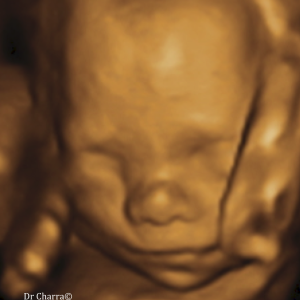

Diplômée en Echographie foetale et Gynécologique

Agrément National pour la réalisation des échographies du Premier Trimestre de grossesse

Membre du Collège d'Echographie Foetale Français (CFEF)